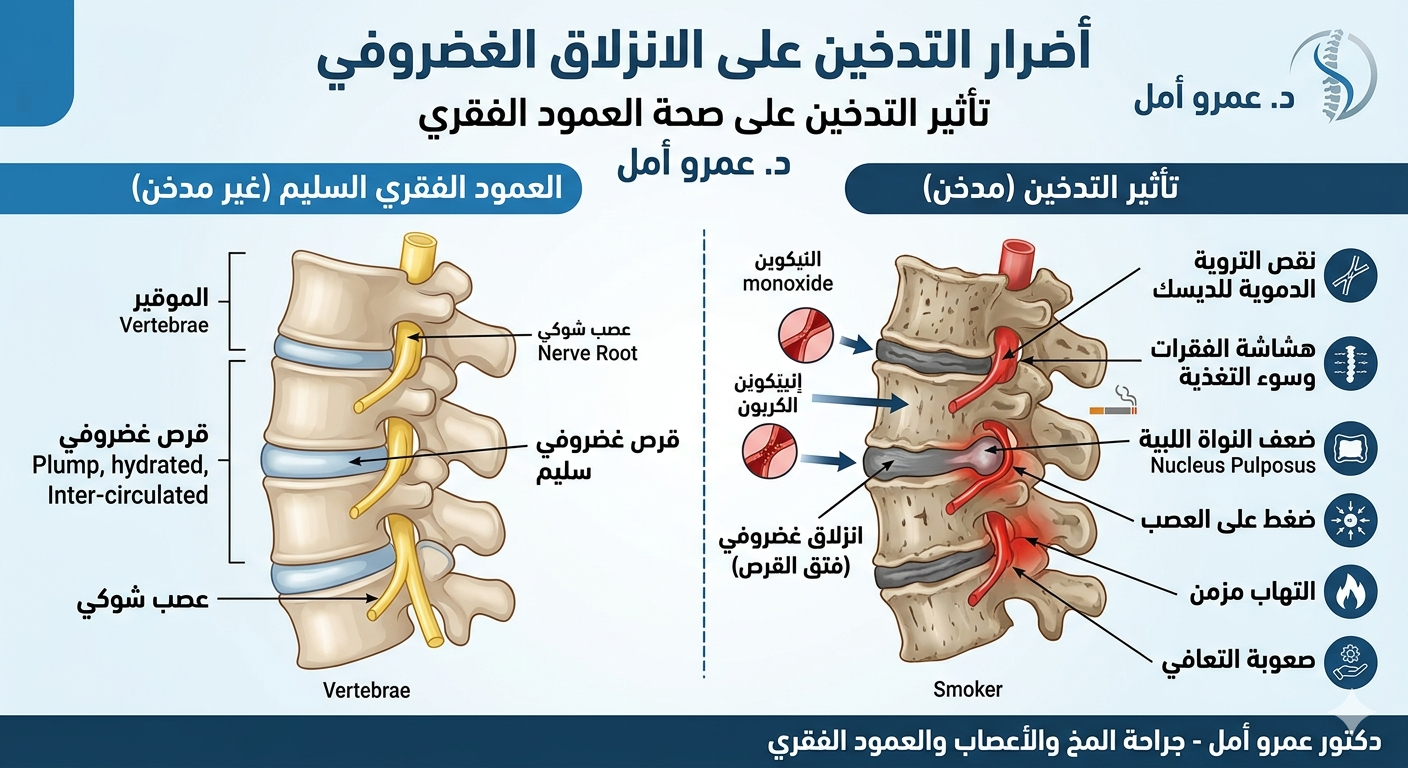

تأثير التدخين على الانزلاق الغضروفي

يؤثر التدخين بشكل سلبي على صحة الغضاريف، لأنه يقلل تدفق الدم والعناصر الغذائية التي يحتاجها الغضروف للحفاظ على مرونته. ومع الوقت، قد يزيد التدخين من فرص حدوث الانزلاق الغضروفي ويزيد من تدهورغضروف الرقبة، كما قد يبطئ الاستجابة للعلاج ويطيل فترة التعافي.

- هل التدخين يؤثر على الانزلاق الغضروفي؟

نعم، التدخين يضعف تغذية الغضاريف ويزيد من فرص حدوث الانزلاق الغضروفي أو تأخر التعافي